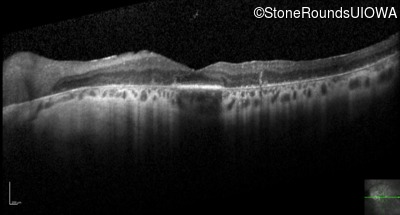

Optical Coherence Tomography - Right - 20/70

Exemplar / OCT Stack